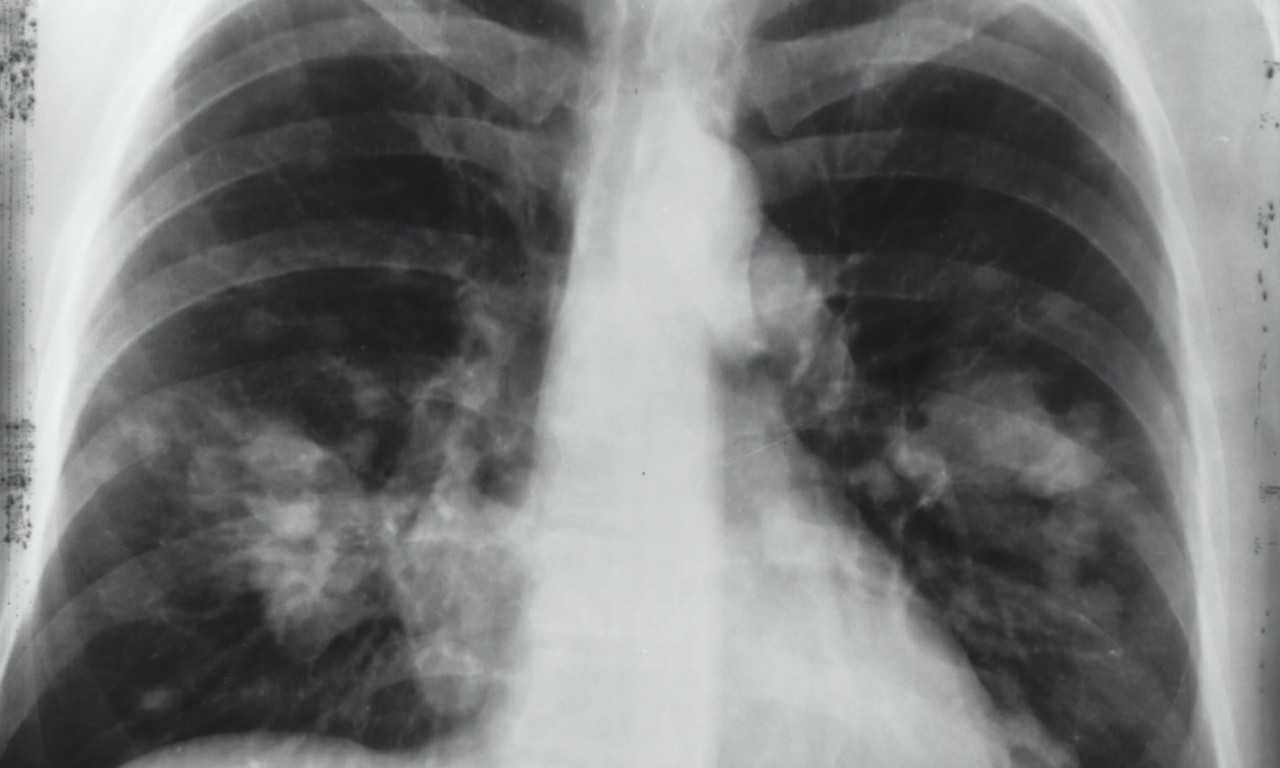

Sa dolaskom jeseni, zdravstveni stručnjaci upozoravaju na pojavu respiratornih virusa, koji uključuju ne samo rino viruse odgovorne za prehlade, već i korona viruse.

Doktor Andrej Trampuž u emisiji "Kec na jedanaest" na televiziji K1, ističe da grip još uvek nije prisutan, ali će se uskoro pojaviti.

- Na jesen dolaze respiratorni virusi, ne samo rino virusi koji uzrokuju prehlade, već i korona virusi. Grip još uvek nije prisutan, ali će doći. Dobra vest je da je trenutna korona varijanta omikronska, koja je vrlo zarazna, ali uzrokuje blage simptome. Zato ne treba da se brinemo - rekao je dr. Andrej Trampuž, dodajući da ova izjava važi i za starije pacijente.

- Korona je malo teža od rino virusa, ali grip je još ozbiljniji. Imamo odlične vakcine i za koronu i za grip, a odgovor na pitanje da li treba da se vakcinišu ljudi je svakako 'da', posebno stariji ili oni sa slabijim imunitetom - dodao je i objasnio o posledicama vakcinacije: